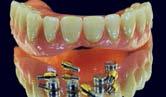

Carga inmediata en fracaso de implantes. Con implantes BLX cigomáticos Straumann Zaga Flat®️ y protocolo

Di gitalArch®️, por e l Dr. Luis Cuadrado de Vicente y cols.